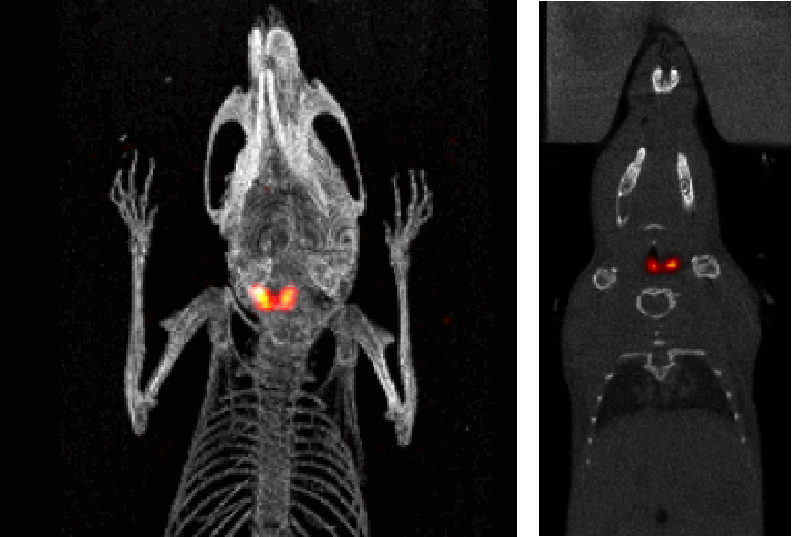

I123小鼠甲狀腺SPECT成像:檢測小鼠的甲狀腺,9.4MBq(250μCi)I123,采集時間:30min。

甲狀腺成像.png